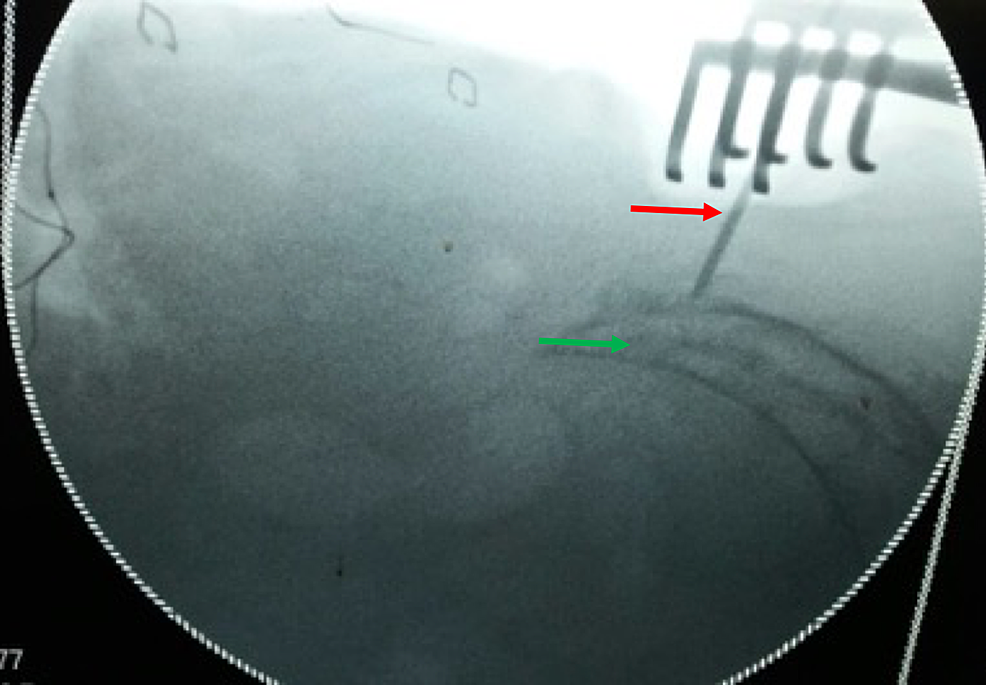

Following pre-anesthesia clearance, bowel was prepared to prevent fecal contamination in case of an unlikely event of a rectal perforation. In the prone position, the buttocks were retracted laterally with adhesive tape to expose the gluteal cleft. The coccygeal and anal regions were prepared with povidone-iodine. Lateral fluoroscopic image was used to locate the S3 level as shown in Figure 2.